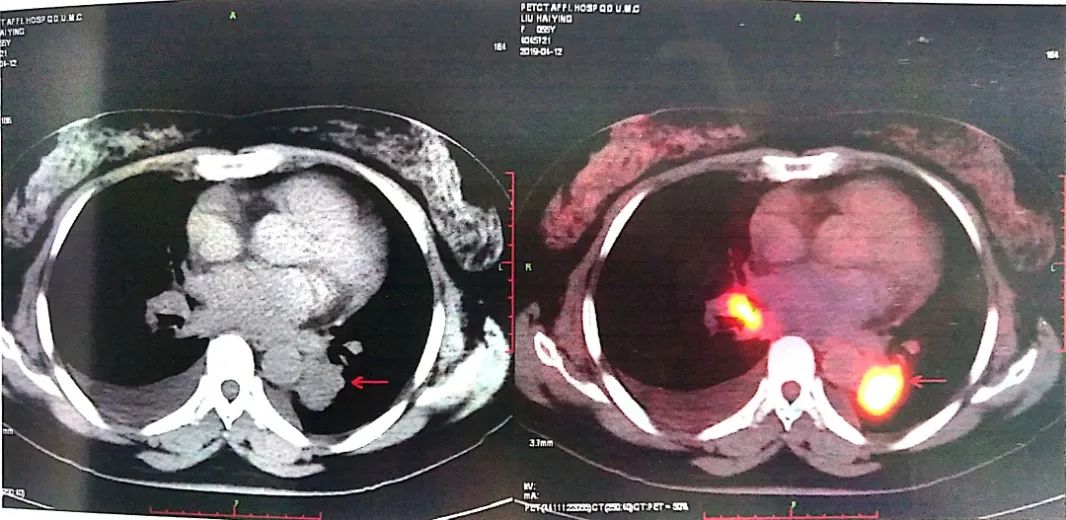

2019-04-12 PET-CT显示①右肺下叶后基底段胸膜下软组织密度肿块(大小26*30mm)。

②左肺下叶纵隔旁软组织密度肿块(大小28*31mm)。

③双肺门、纵隔内隆突下、气管旁、主肺动脉窗、血管前间隙、右侧颈部Ⅴ区及锁骨区多发增大淋巴结。

在经过一段时间治疗后,患者出现治疗分离反应

(其颅内转移灶处于大PR状态,但肺部病灶从散点状变成弥漫状态)

在确认患者进展后,我们进行了进展病灶的穿刺并进行基因检测,发现了包括ALK融合CRKL、MAPK3等多靶点的突变。